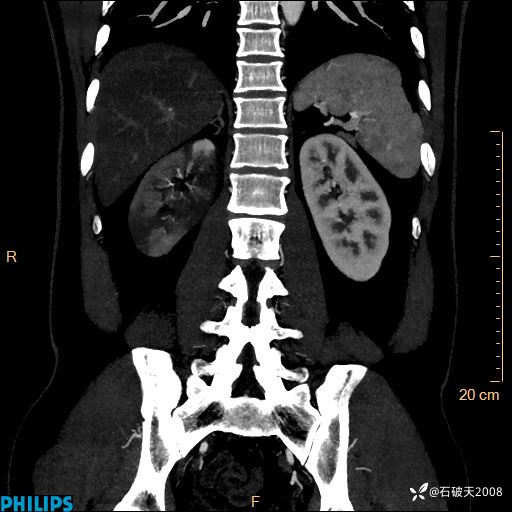

增强轴位

冠状位